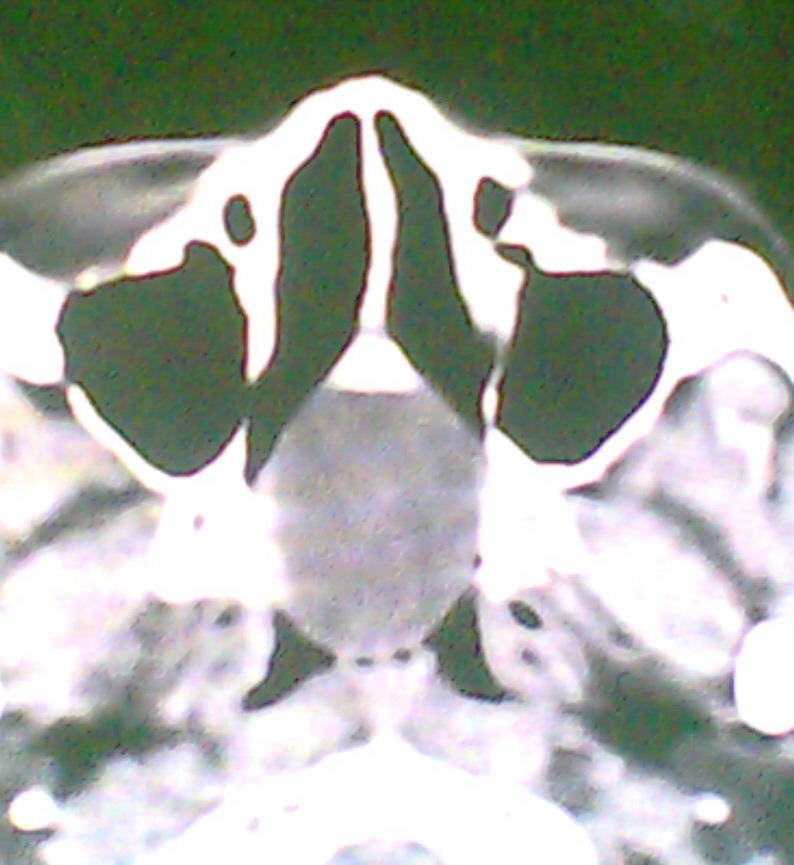

女、18岁,身高1.5左右,鼻塞、流涕数月,两侧瞳孔明显增大,曾与几年前去北京看眼,未发现病变。

考虑起源与蝶窦的粘液囊肿。

考虑脑膜脑脊液鼻内膨出

考虑起源于蝶窦的粘液囊肿突入鼻咽部。

\"几年前去北京看眼\"不知这句话有何玄机,支持考虑脑膜脑脊液鼻内膨出,膨出口在蝶鞍处

建议冠状面扫描,支持:脑膜鼻内膨出; 蝶窦粘液囊肿突入鼻腔可能性小。

在上级医院冠状位ct扫描后,诊断为:脑膜膨出,已住院准备手术。等待术后结果。